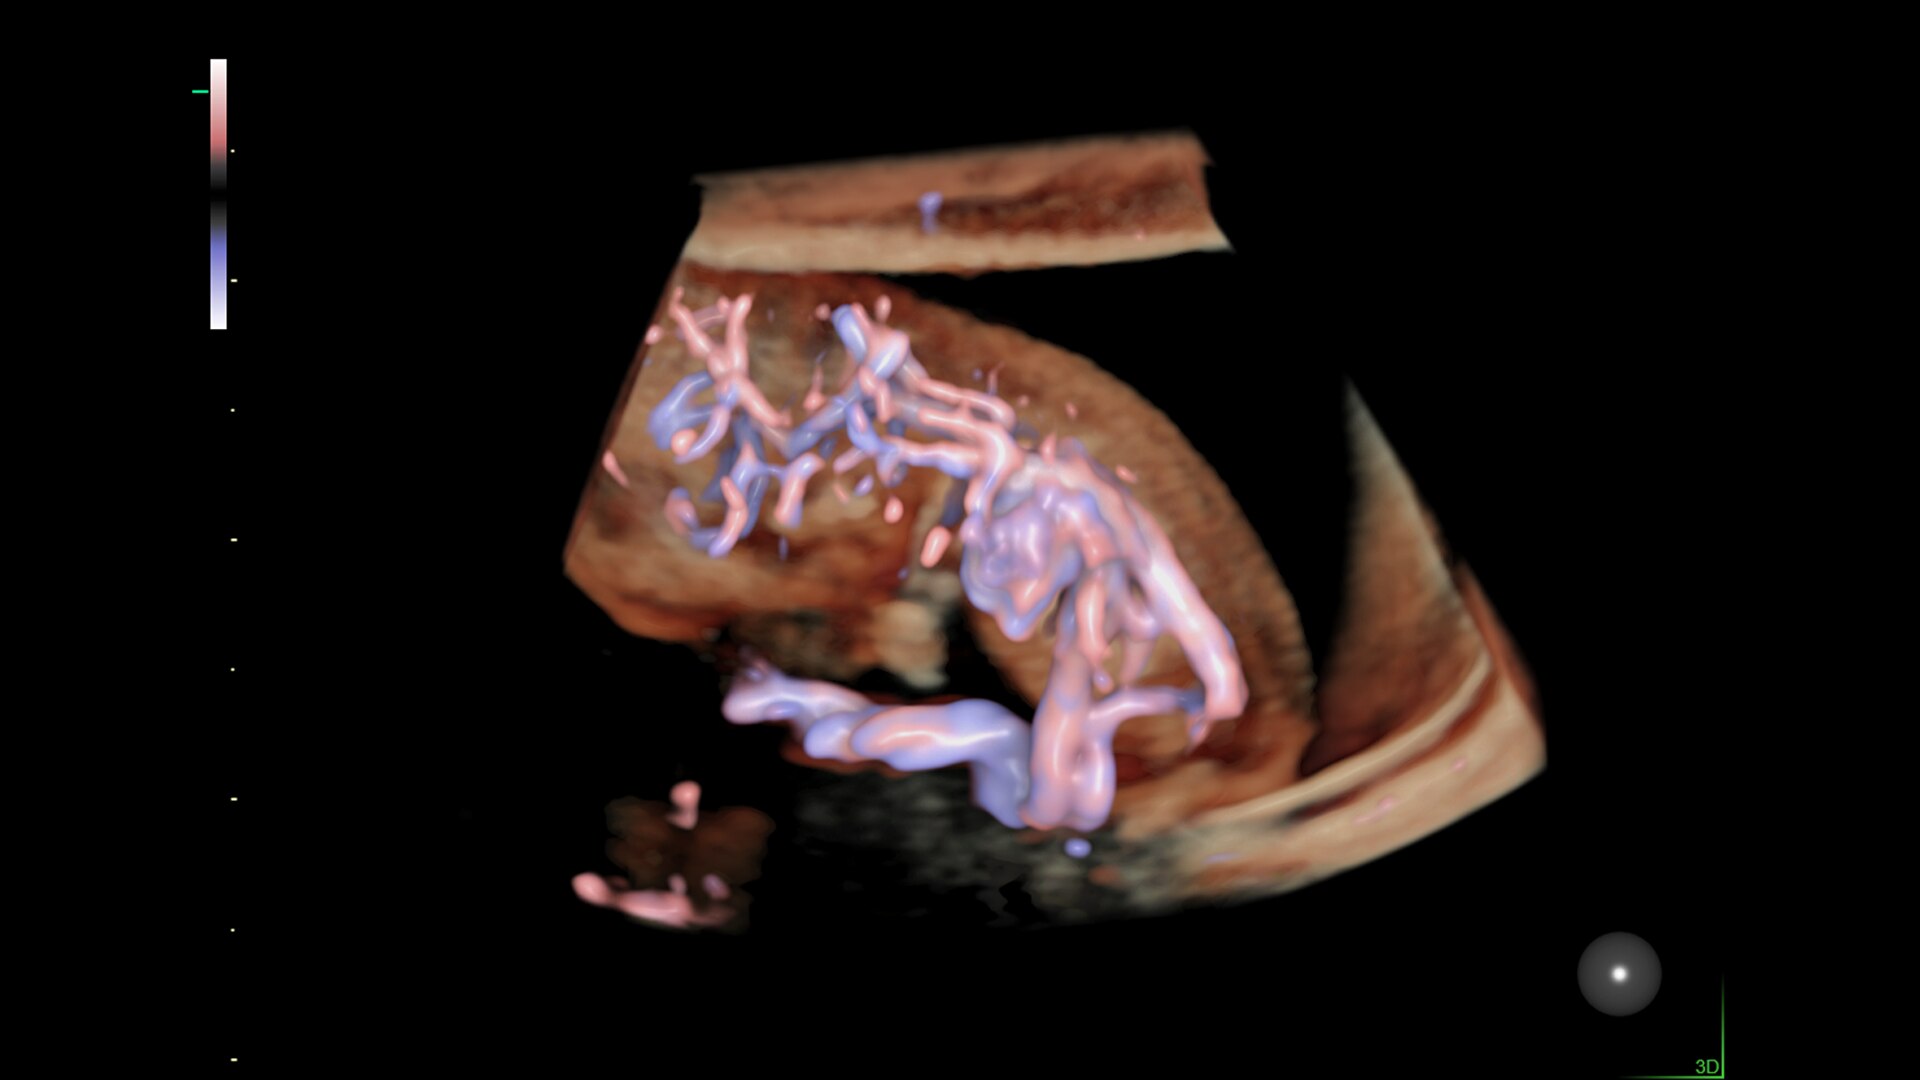

Enhanced Volume Imaging

Deliver next generation 3D/4D & Color images with HDlive Studio+

Hemodynamic Visualization

Provides a graphical representation of the trajectories of the blood cells in real-time to visualize complex blood flow quickly and clearly, helping you to differentiate normal from abnormal hemodynamics